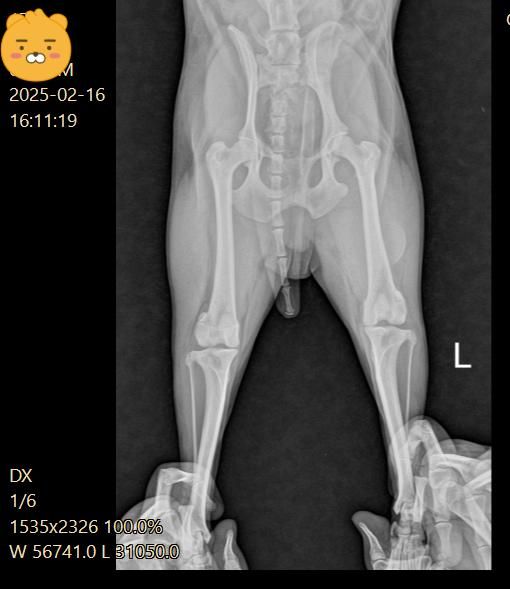

강아지 십자인대 파열로 볼 수 있나요? (엑스레이 첨부)

5일 간격으로 엑스레이를 찍었어요

첫 진료 당시 십자인대 부분 파열이라고 했는데

(첫번째 진료)

우측 관절낭이 좌측에 비해 종창 되어 관찰되고 경골 경사면 각도가 비교적 크게 관찰되어 십자인대에 손상이 있을 가능성이 있는 사진입니다. 이를 확인하기 위해서는 MRI 촬영이 필요하지만 현실적인 검사 방법은 아니라 추정일 뿐입니다. 하지만 방사선학적 관점에서 십자인대의 인장성 손상은 합리적인 추론입니다.